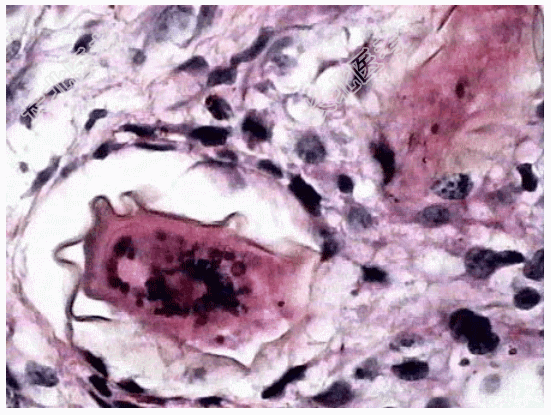

- [材料题] 患者,男,50岁,湖南岳阳人。因贫血、白细胞、血小板减少并腹水入院,临床诊断为“肝硬化”。肝穿刺活检镜下观如图所示,临床拟诊血吸虫性肝硬化。

- 简答题2、该疾病病理学改变表现为?